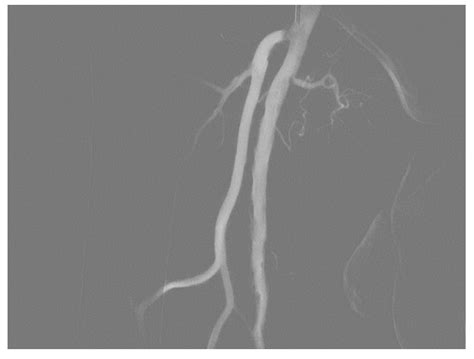

• Computed Tomography Angiography (CTA): This non-invasive imaging technique uses CT scans to create detailed images of the arteries. It can detect blockages, aneurysms, and other abnormalities.